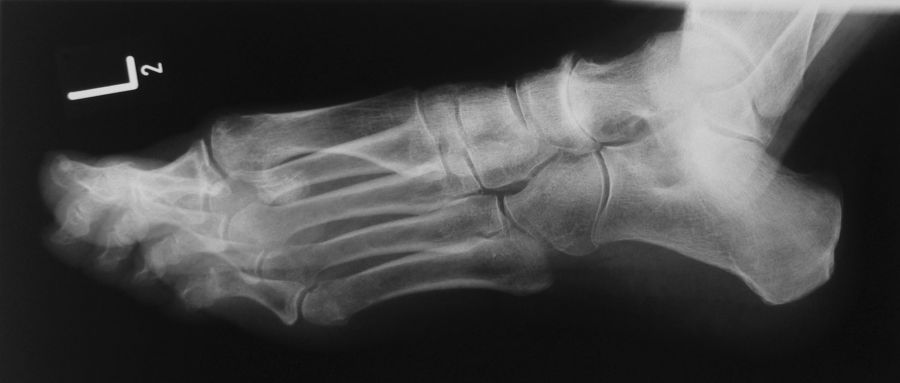

Alte Impressionsfraktur des Os cuboideum mit schweren Knorpelschäden.

Abbildung 9

Die isolierte Arthrose des Calcaneocuboidal-Gelenkes (CC-Gelenk) ist sehr selten. Mögliche Ursachen sind Traumen mit gewaltsamer Abduktion des Mittelfußes gegenüber dem Rückfuß. Der hierfür typische Unfallmechanismus wird meistens bei Zweiradfahrern vorgefunden 33. Impressionen der Gelenkfläche, Ausrisse des Processus anterior calcanei (Insertion des Ligamentum bifurcatum), sowie eine posttraumatische Instabilität des Gelenks können zu degenerative Veränderungen führen.